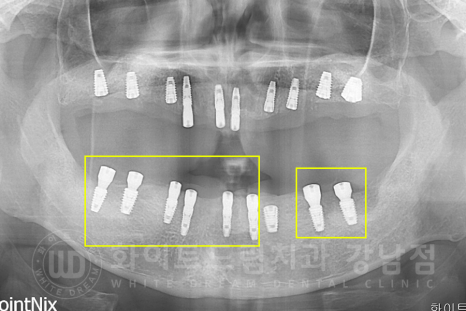

▲ 노란색으로 표기된 부분이 1+2차 수술을 동시 진행한 임플란트입니다. (하악)

상악동 거상술을 진행한 부위를 제외하고 거의 모든 임플란트를 이 방식으로 진행했습니다.

1차 수술은 임플란트를 잇몸뼈 안에 심는 것이고,

2차 수술은 보철을 부착할 수 있도록 잇몸 밖으로 꺼내는 술식입니다.

이 1차, 2차 수술을 동시에 진행하면, 따로 2차 수술을 진행할 필요가 없기 때문에

기간과 내원 횟수가 줄어드는 장점을 가지고 있죠.